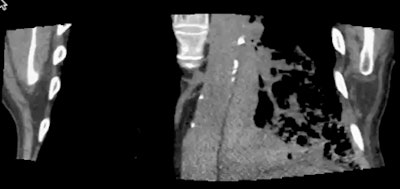

| In a patient with a left lower adenocarcinoma, conventional staging CT was unable to exclude invasion of the left lateral aspect of the aorta. However, static images (one at extreme inspiration and one at extreme expiration, above) and two coronal video files (below) confirm differential motion, and the tumor was confirmed at surgery. Images and cine clips courtesy of Dr. John Troupis. |